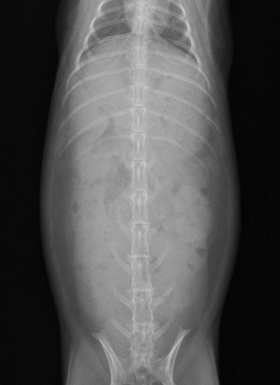

ウサギの腰椎骨折

四肢と同様に背骨も骨折してしまうことがあります。脊髄を圧迫してしまう為、排便・排尿困難や、後肢麻痺がおこります。

骨折当初は痛みが強く、食欲が落ちることが多いです。内科的に痛みのケア、食事と排泄のサポートをしていきます。

骨折する1年前のレントゲン

骨折後のレントゲン(前方の腰椎が折れ、背側にずれています)

ほとんどの場合、後肢の麻痺は残ります。

適切なケアを行うことで元気に生活できる場合もあり、根気強く治療をしていきます。